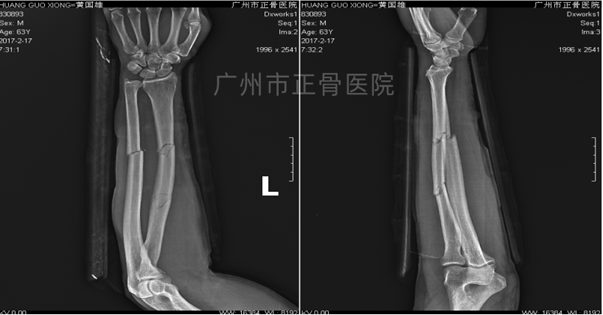

▲3天后复查见尺骨移位

▲手法调整后加石膏托固定